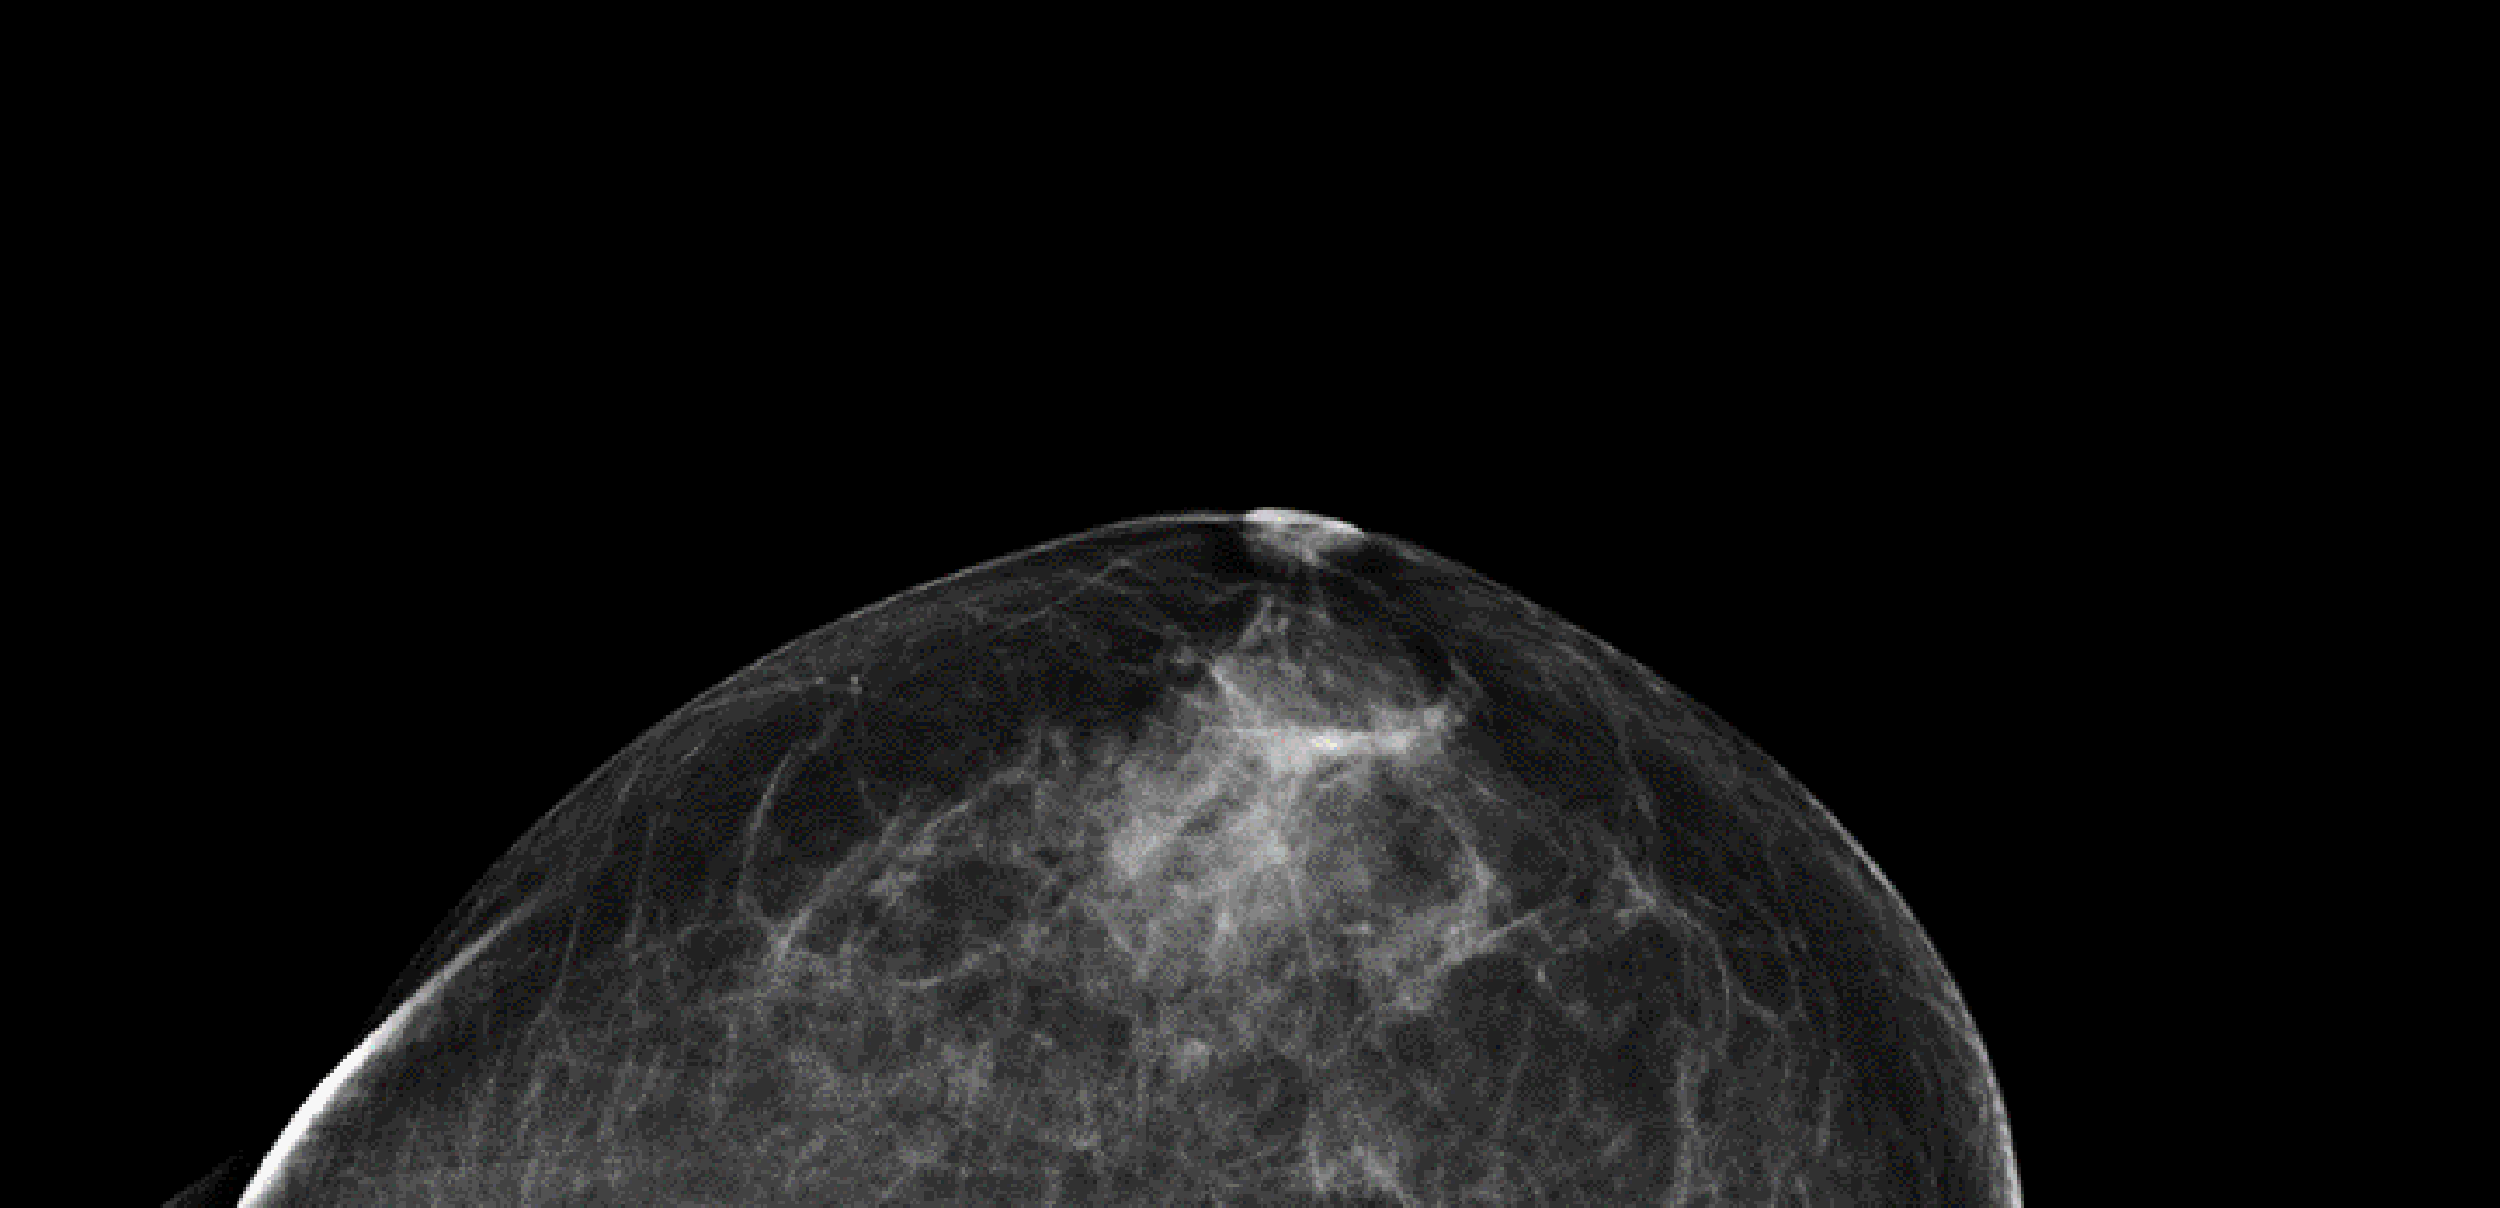

Enligt en utvärdering från Socialstyrelsen minskar mammografi dödligheten i cancer med 16 procent i åldersgruppen 40-49 år och drygt 20 procent i guppen 50–74 år. Röntgenbilden visar ett bröst utan cancer fotograferat uppifrån. De mörka partierna är fettvävnad och de vita kärl- och bindvävnad.